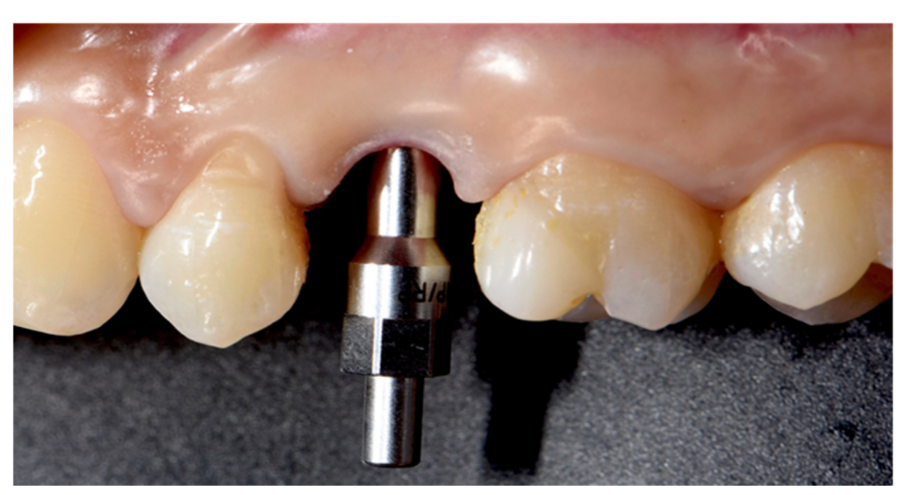

Implants fracture is an untreatable condition. There are several tools that may help clinician to remove the implant. However, fractured implant often presented damaged implant-abutment connection, hence, implant retrieval tools/kits (Figures 1–4) may not work. In cases implant is severely damaged and/or the residual osseointegration is very strong, such us in the mandible, the only possibility is to use a trephine burs (Figures 5–10).